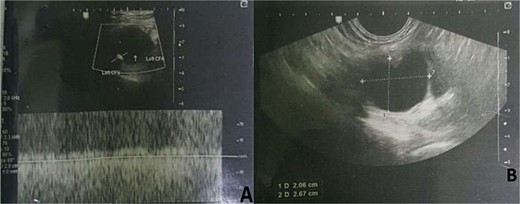

Up on surgical side evaluation, there was a 3 × 2 cm inguinal, slightly tender, firm mass with associated ipsilateral swollen leg. There was a leg-leg discrepancy of 5 cm and 2 cm at the calf and mid-thigh, respectively. His Doppler ultrasound showed left inguinal cystic mass (2.5 cm × 2.4 cm) in the femoral sheath compressing the CFV, but without communication. The blood flow in the compressed CFV was sluggish with no evidence of DVT (Fig. 1). CT venography also showed similar results (Fig. 2). He was then admitted to the surgical ward with the radiologist’s and operating surgeons’ impression of adventitial cystic disease (ACD) of the CFV, and he was scheduled for surgical excision of the presumed ACD.

CT Venography with a possible left common femoral vein adventitial cystic disease.